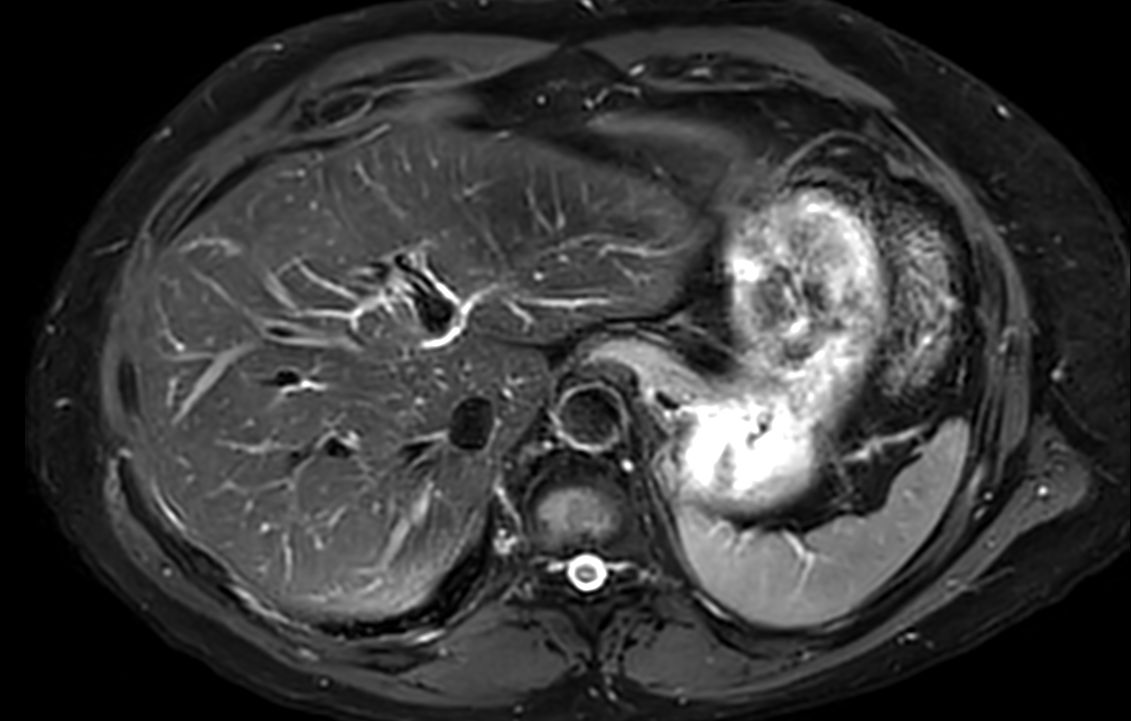

Axial T2w TSE mDIXON (in-phase)SmartSpeed MotionFree